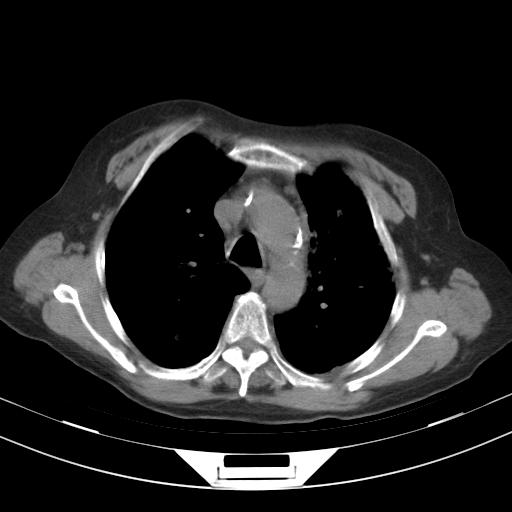

老年女性,嗜睡3天,意识模糊。轻咳,无发热。

甲流?

1)两肺感染性病变;建议抗炎治疗后复查。2)纵隔淋巴结肿大。3)左侧胸腔积液。

2)纵隔淋巴结肿大。